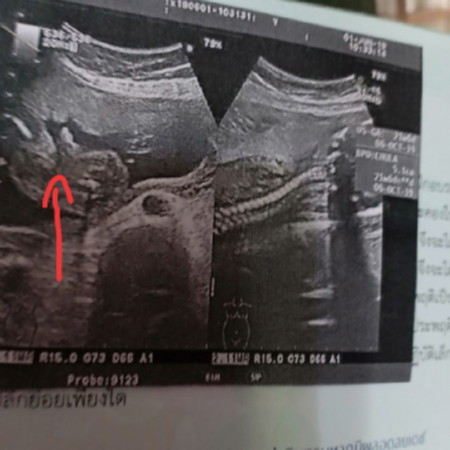

หมอบอกน่าจะเป้นผู้ชายแต่ไม่100%

แม่ๆลองดูใบซาวด์หน่อยค่ะ ว่าชายรึป่าว ส่วนตัวอยากได้ชายค่ะ แต่ไม่อยากคาดหวัง กลัวผิดหวัง ฝากแม่ๆดูหน่อยค่ะ ในใบซาวด์

แบบนี้ชายหรือหญิงคะ แม่ๆช่วยดูหน่อยจ้า. หมอบอกว่าหญิง 100% แต่เราไม่ค่อยมั่นใจ

ชายคร้า บ้านนี้ก็มีโผล่ออกมาเหมือนกันเลยคะ

ลูกกลมๆ นั้นไข่ผมเองครับ ผู้ชาย100%

ของเราก้ชายจ้า ชาย100%